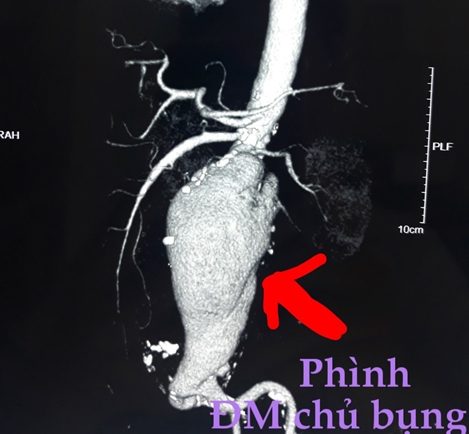

Người bệnh được chụp CT-scan có bơm cản quang. Kết quả hình ảnh cho thấy động mạch chủ bụng bị thủng 1 lỗ đường kính khoảng 2cm, tạo thành túi phình giả quanh động mạch chủ kích thước lớn, đường kính 6,5cm kéo dài 8,8cm. Các bác sĩ chẩn đoán đây là một trường hợp nhiễm trùng sau phúc mạc, ổ nhiễm trùng ăn thủng động mạch chủ bụng dưới thận tạo thành túi phình giả, nguy cơ vỡ khiến người bệnh tử vong bất cứ lúc nào.